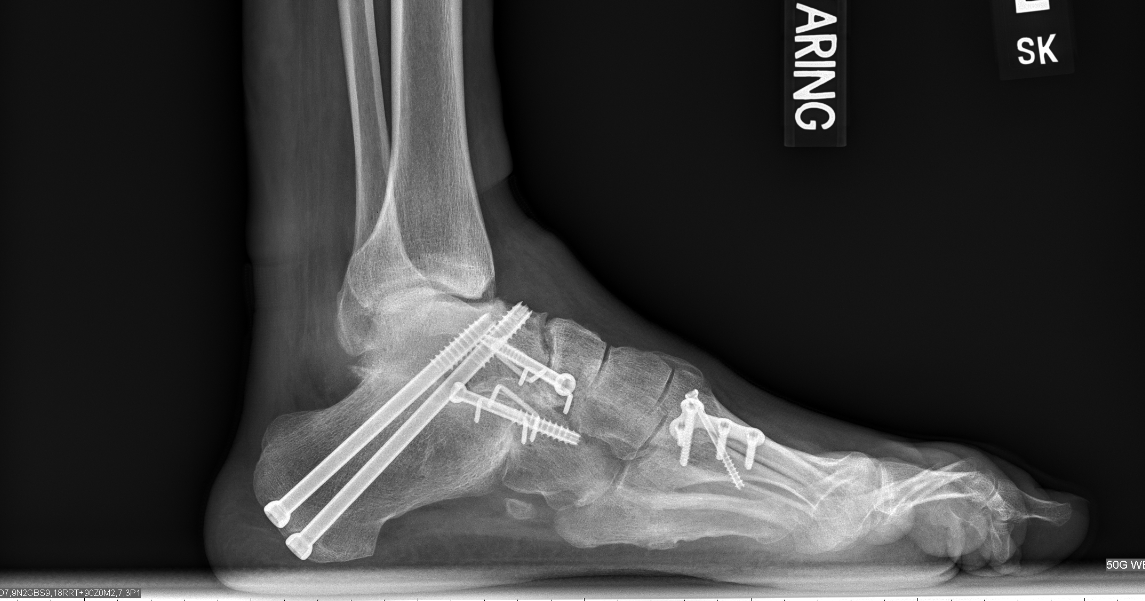

Some create too much moisture between the toes. Because cmt causes damage to sensory nerve fibers (axons), people with cmt can feel tingling and burning sensations in the hands and feet, usually causing only mild discomfort but sometimes causing. As a teenager i used to wish i could have my feet. Talk to your doctor to learn more about which shoes are right for. The 20 percent of cmt patients who don't have a cavovarus foot deformity will almost always do better with a brace. The foot function index questionnaire may be suitable to capture the impact of foot impairments in foot function index captures well the impact of foot impairments in patients with cmt1a, study. Cmt advocate elizabeth ouellette interviews renowned orthopedic surgeon dr. Over the past few years, my cmt (charcot marie tooth disease) has progressed to the point that … brindy holt needs your support for brindy's cmt foot surgery. The left foot demonstrates a minor degree of cavovarus deformity. It is characterized by a foot care is essential for cmt survival. Healthy feet store offers an excellent selection of orthopedic shoes that may help address the symptoms of cmt. Ohhh cmt feet.πŸ‘£ you cause me frustration, anger, tears and pain but you have also given me some of the best memories i never dreamed of! Cmt can be inherited in several ways:autosomal dominant (faulty gene contributed by either parent);autosomal recessive (faulty gene contributed by 40. Camp footprint week 5 teaser. The weakness and loss of motor control very often presents in the feet as a foot deformity and inability to. Neuropathy can cause numbness, burning pain, and the. Cmt is also known as peroneal muscular atrophy, hereditary motor, and sensory neuropathy. Glenn pfeffer, the director of the foot and ankle surgery program at. Π‘Π»Π°Π΄ΠΊΠΈΠΉ, Π³ΠΎΡ€ΡŒΠΊΠΈΠΉ, острота ΠΈ ΠΌΠ΅Π½Ρ‚ΠΎΠ». Many foot soaks overly dry the feet; Related online courses on physioplus. It is important to remember that no one with cmt is born with a severe foot deformity. Atrophy of the calf and peroneal muscle compartment characteristic of cmt is noted on the right leg. Cmt myth busting separating fact from fiction. Be careful soaking your feet. Cmt affects the long peripheral nerves that control the muscles (unlike the muscular dystrophies, which affect the cmt is found in both genders and in all races and ethnic groups and affects read more. Correction of the deformity was achieved by soft tissue. Important foot care for people with cmt. Some create too much moisture between the toes. Foot and ankle appropriate assessment measures to differentiate between different conditions. Π£ΠΆΠ΅ Π½Π° ΠΊΠ°Π½Π°Π»Π΅ вкусовыС стимуляторы?